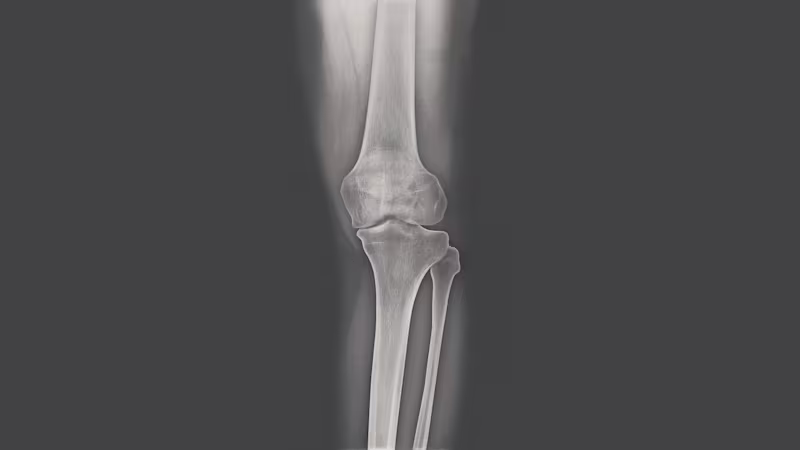

Once your doctor has finished asking questions, they will generally turn their attention to the affected joint. Using palpation, they will see how sensitive you are to pressure. They will also look closely at visual anomalies such as swelling, joint effusions and axial malalignment (knock knees or bow legs) to determine whether symptoms are caused by osteoarthritis of the knee. Additional examinations will be required before your doctor can confirm the diagnosis. X-rays are generally used for this purpose. An expert can use X-ray images to determine whether joint cartilage displays irregularities or cracks, or whether osteophytes (bone spurs) have formed. The doctor can also refer you for a CT, MRI or ultrasound examination. Depending on the method used, doctors can detect bone changes, damage to the meniscus or cruciate ligament, and irregularities in the cartilage of your knee joint.

Diagnosing osteoarthritis of the knee

When talking to the physician, you should give a detailed description of your knee problems and answer the physician's questions precisely. In addition to the knee disorder, other health information such as osteoarthritis in other joints, injuries, infections or chronic diseases may also be relevant to knee pain. While performing the examination, the physician will look at the knee and check its functions. He will then x-ray it to see if any visible changes have already developed in the joint. In some cases, further examinations will be necessary to reach a diagnosis. Depending on the case, these include, for example, examinations of the blood or the joint fluid as well as other imaging procedures.